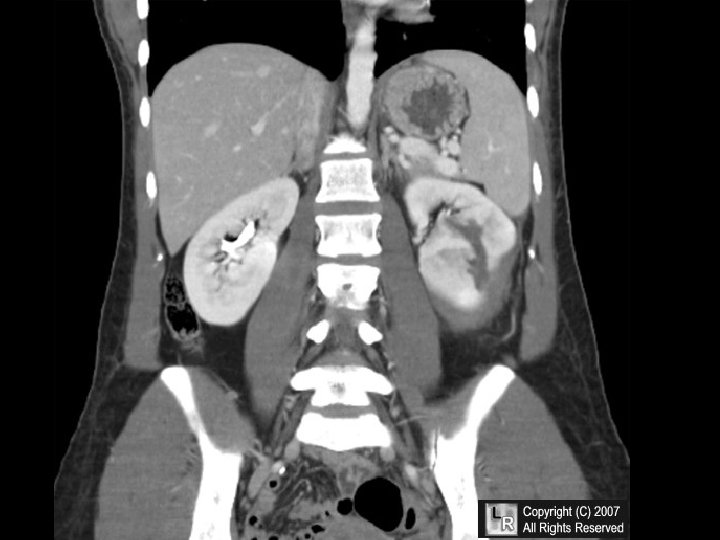

RENAL EDEMA • SODIUM RETENTION • PROTEIN LOSING GLOMERULOPATHIES (NEPHROTIC SYNDROME)

ATN